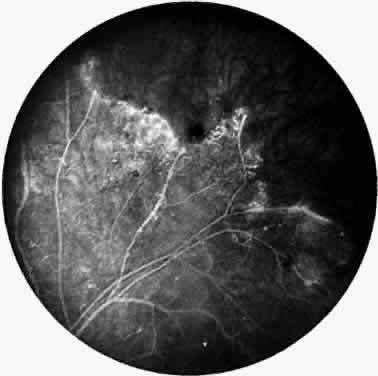

Elliot and Spitnas and colleagues have documented the abnormalities at the junction between the anteroperipheral nonperfused and the posterior perfused retina.9,10 Intraretinal hemorrhages often first appear in the affected area, followed by an increase in vascular tortuosity with frequent collateral formation around occluded vessels (see Fig. 3). Microaneurysms, arteriovenous shunts, and venous beading are commonly seen at the junction (Fig. 4). Fluorescein angiography enhances these abnormalities and often demonstrates staining at the stumps of obliterated vessels.

Fig. 4. Fluorescein angiogram demonstrating severe nonperfusion involving the macula. In this case, the macular nonperfusion was responsible for loss of central vision.

As a result of the retinal nonperfusion, new vessels can form either on the disc (neovascularization of the disc) or, more commonly, neovascularization can occur elsewhere in the retina (Fig. 5). These abnormal blood vessels can hemorrhage and are the major cause of visual loss in this disease. The neovascularization in the peripheral retina usually occurs at the junction of perfused and nonperfused retina, similar to the appearance of neovascularization in the peripheral retina in diabetic retinopathy and the other peripheral proliferative retinopathies. Neovascularization can be associated with extensive fibrovascular proliferation and fibrosis (Fig. 6). The anteroposterior and tangential traction resulting from the fibrovascular proliferation places these eyes at risk for development of retinal detachment. Neovascularization of the iris also has been described.

Most patients with Eales' disease retain at least reading acuity in one eye, but a few patients become legally blind. Severe visual loss usually results from complications associated with neovascularization, such as persistent vitreal hemorrhage, retinal detachment, and neovascular glaucoma. Occasionally, loss of vision is caused by cystoid macular edema, macular holes, retinal telangiectasia, or epiretinal membrane. In some patients, relentless nonperfusion progresses across the macula (see Fig. 4); visual acuity in these eyes usually is less than 20/400.